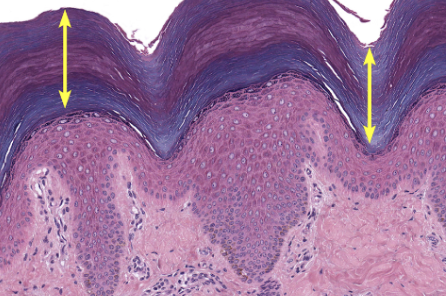

Layers of the epidermis - thick skin

Stratum corneum

Stratum lucidum

Stratum granulosum

Stratum spinosum

Stratum basale

dead flat layer of keratinocytes

thick in thick skin, thin in thin skin

ONLY in thick skin (eg. palms, feet)

doesn’t grow hair

layer lacks cell nuclei + organelles

dark line layer